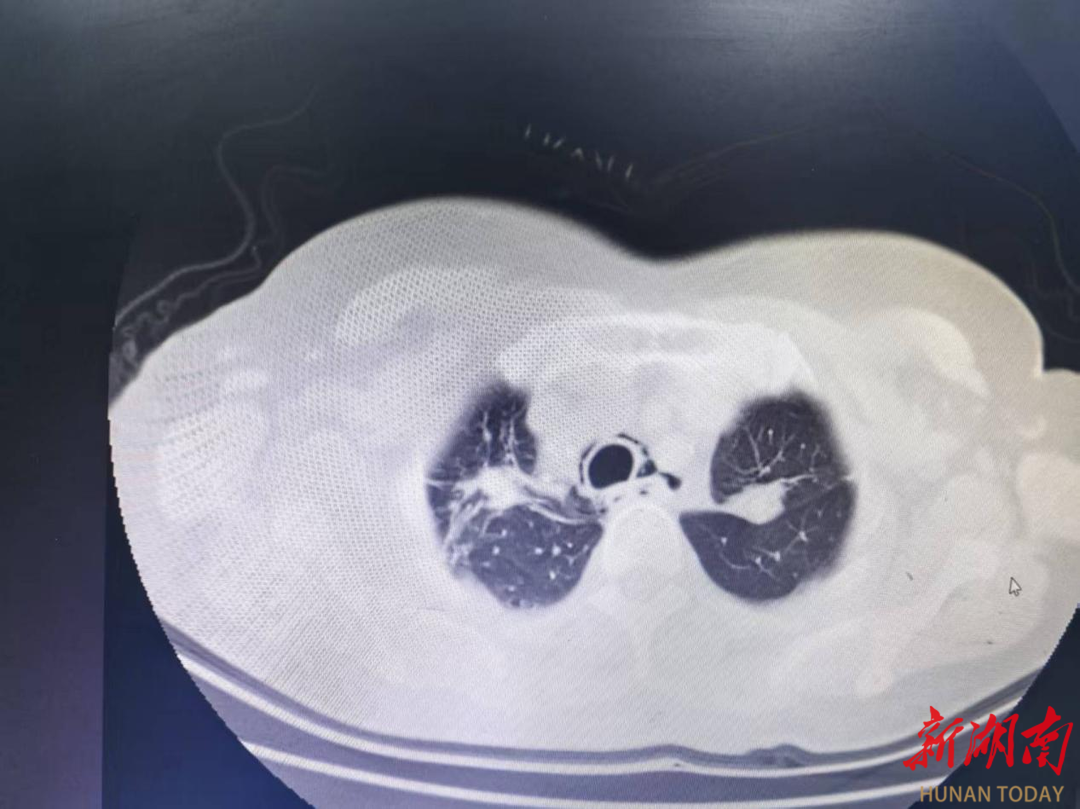

术后影像图。

术后复查CT显示,孙奶奶仍伴有纵隔气肿和双肺炎症。针对这一情况,医护团队随即为她量身定制了综合治疗方案:严格禁食让消化道充分休息,强力抗感染抑制炎症扩散,全面营养保障机体需求,同时辅以消除咽喉水肿、强化口腔护理等措施。在医护人员的细致监测与精心照料下,孙奶奶的病情逐步好转,术后两三天便能少量进食,最终完全恢复正常饮食,无任何不适,顺利出院。